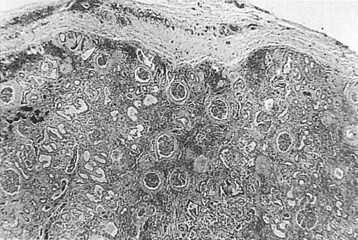

The opportunity for pathologic confirmation of acute bacterial nephritis is rare. The kidney may be edematous. Focal acute suppurative bacterial nephritis caused by hematogenous dissemination of bacteria to the renal cortex is characterized by multiple focal areas of suppuration on the surface of the kidney (Fig. 10–15). Histologic examination of the renal cortex shows focal suppurative destruction of glomeruli and tubules. Adjacent cortical structures and the medulla are not involved in the inflammatory reaction. Acute ascending pyelonephritis is characterized by linear bands of inflammation extending from the medulla to the renal capsule (Fig. 10–16). Histologic examination usually reveals a focal wedge-shaped area of acute interstitial inflammation with the apex of the wedge in the renal medulla. Polymorphonuclear leukocytes or a predominantly lymphocytic and plasma cell response are seen. Bacteria also may be present.

Figure 10–16 Acute ascending pyelonephritis. A, Cortical structures, tubules, and collecting ducts diffusely infiltrated with inflammatory cells. B, Section of the renal cortex showing wedge-shaped destruction of renocortical structures as a result of ascending infiltration with inflammatory cells. C, Thickened and inflamed tissue surrounding the collecting ducts in the medulla. A polymorphonuclear cast of segmented neutrophils is clearly visible.

(From Schaeffer AJ. Urinary tract infections. In: Gillenwater JY et al, editors. Adult and pediatric urology. Philadelphia: Lippincott Williams & Wilkins; 2002. p. 211–72.)